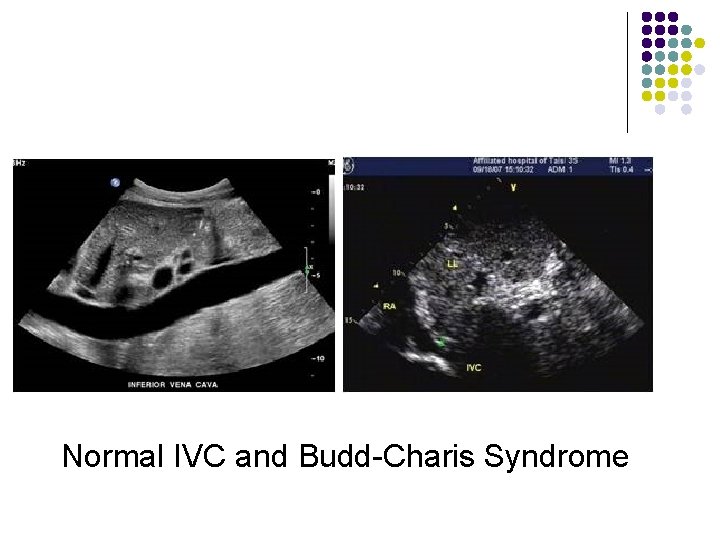

Normal IVC and Budd-Charis Syndrome